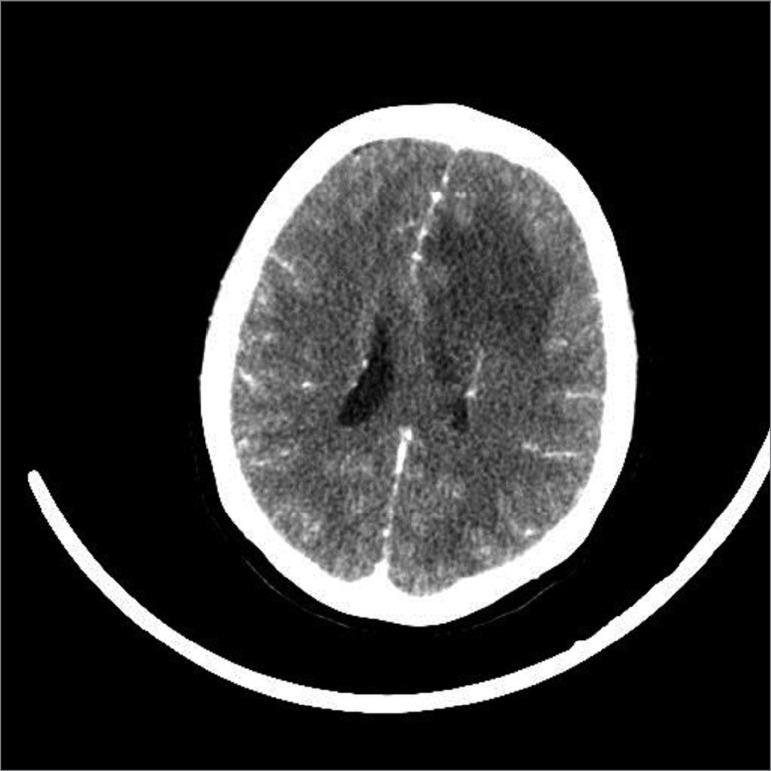

We report on the case of a 29-year-old woman recently diagnosed with systemic lupus erythematosus with hematological, cutaneous, serous and renal manifestations (class IV lupus nephritis), who underwent corticosteroid pulse therapy and mycophenolate induction therapy. After 3 months of evolution, she developed headache and altered mental status. Computed tomography showed an area of hypoattenuation in the left frontal white matter and her cerebrospinal fluid examination showed pleocytosis and hyperproteinorrhachia. Peripheral blood and CSF culture identified Listeria monocytogenes. The patient presented deterioration of her neurological status, requiring invasive mechanical ventilation, monitoring of intracranial pressure and, despite all the intensive support, persisted in a comatose state and developed multiple organ failure, evolving to death due to nosocomial bloodstream infection.

我们报告了一例 29 岁女性系统性红斑狼疮病例,该患者有血液学、皮肤、浆膜和肾脏表现(狼疮肾炎 IV 级),接受了皮质类固醇脉冲治疗和吗替麦考酚酯诱导治疗。在 3 个月的病程中,她出现头痛和精神状态改变。计算机断层扫描显示左额叶白质有一处低衰减区,脑脊液检查显示白细胞增多和高蛋白血症。外周血和 CSF 培养鉴定出单核细胞增生李斯特菌。患者出现神经状态恶化,需要进行有创机械通气、颅内压监测,尽管进行了所有强化支持,她仍处于昏迷状态并发生多器官衰竭,最终因院内血流感染而死亡。